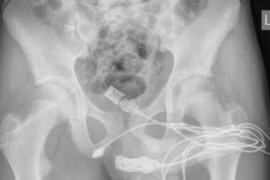

Can thiệp chỉnh sửa bộ phận sinh dục

Có rất nhiều lựa chọn khi xem xét phẫu thuật thẩm mỹ bộ phận sinh dục. Nghiên cứu trước và thăm khám, tư vấn sẽ giúp bạn và bác sĩ phẫu thuật xác định mục tiêu và lập kế hoạch để đạt được kết quả tốt nhất có thể.